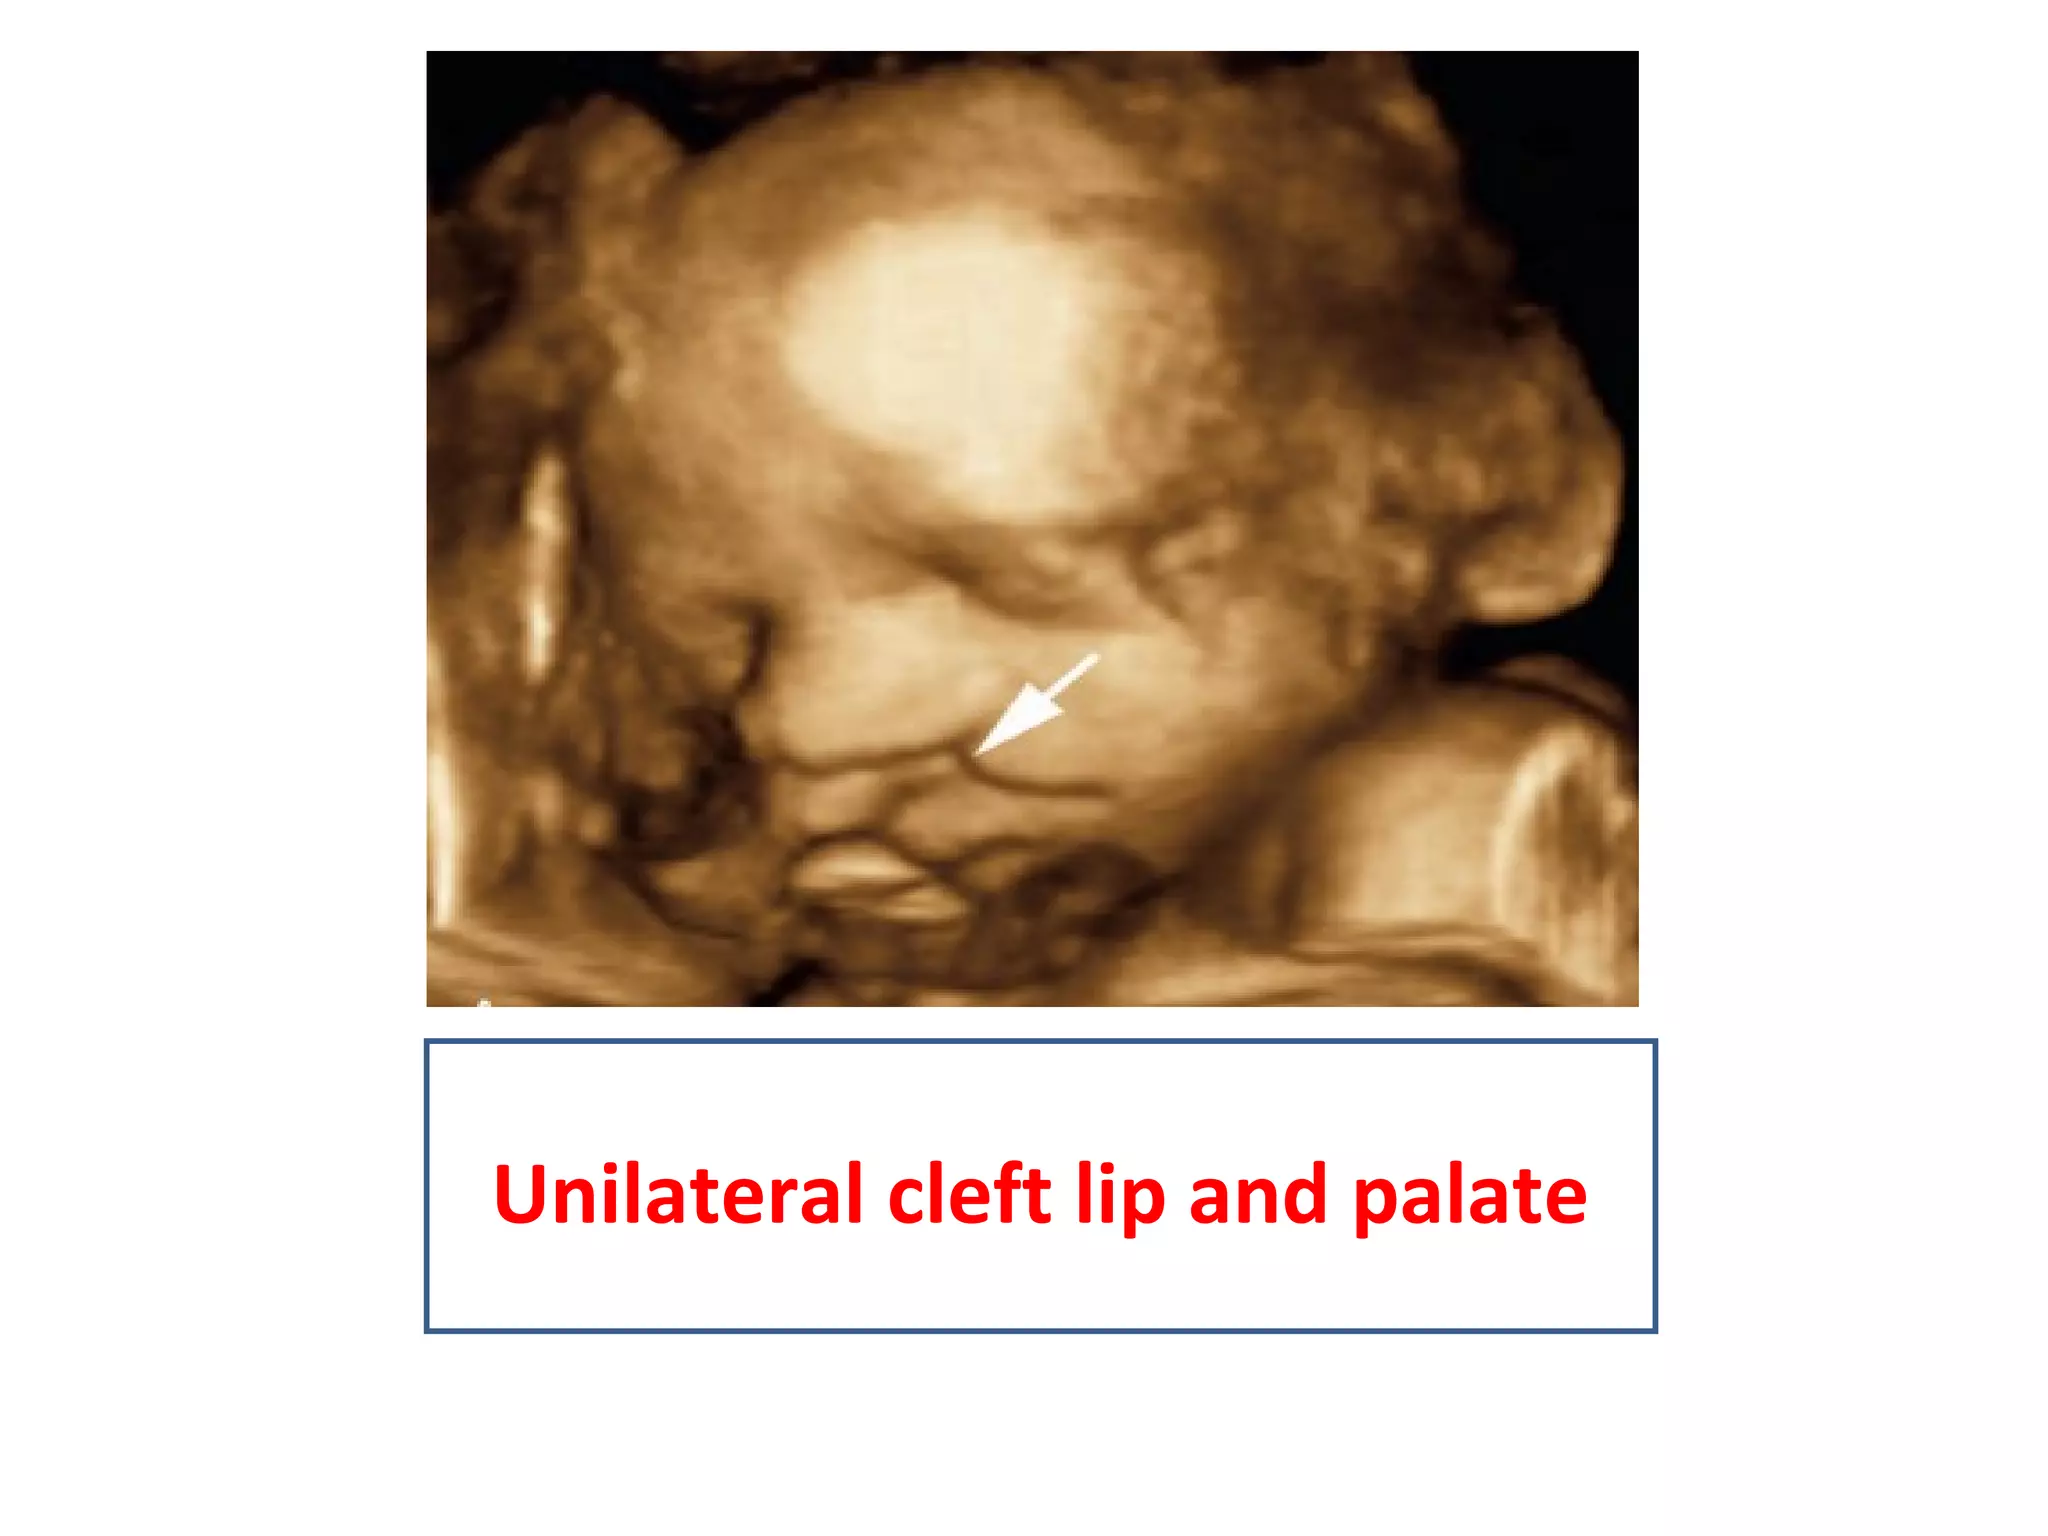

Midline facial defect trisomy 13

Unilateral cleft lip and palate

• Especially helpfulin evaluation of congenital anomalies of fetus, uterine anomalies,adnexal lesions ,ectopic pregnancy ,localization of iucds.